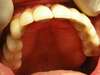

cas n°2 : Péri-implantite